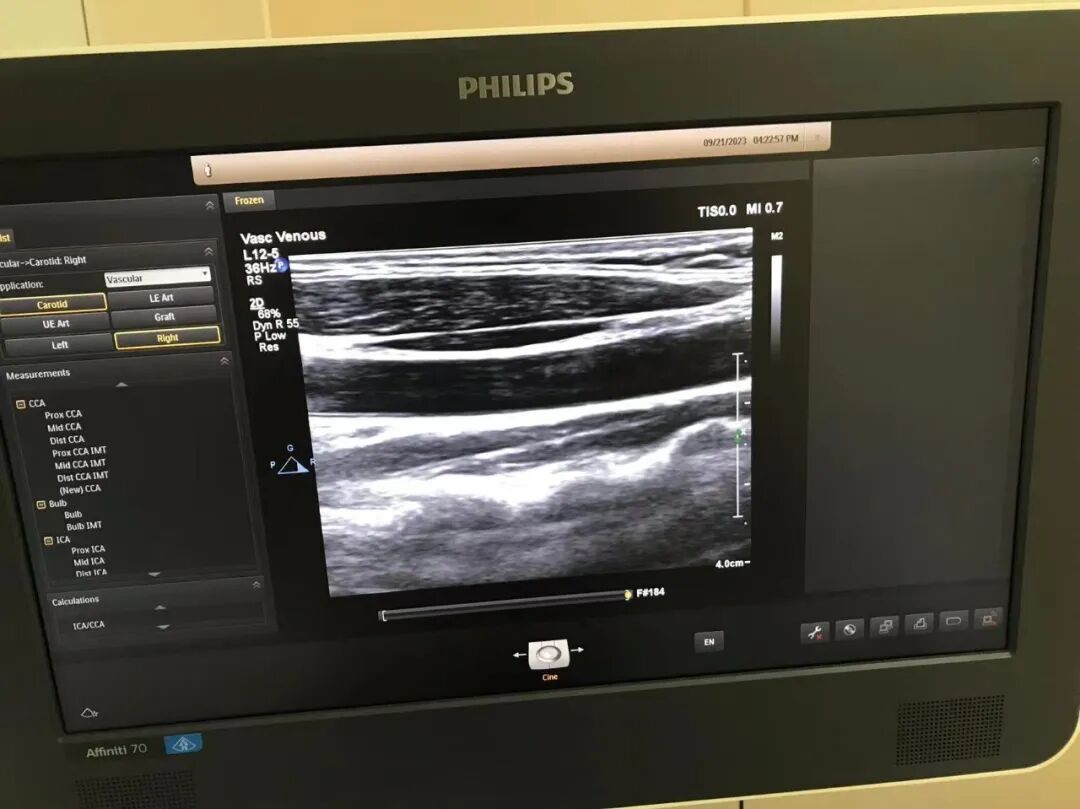

4.故障处理

更换声头,之后发现电缆线断裂有暗道,更换电缆线。

5.维修后效果

为什么要维修探头飞利浦高频探头L12-5故障维修案例_https://www.jmylbn.com_新闻资讯_第3张

为什么要维修探头飞利浦高频探头L12-5故障维修案例_https://www.jmylbn.com_新闻资讯_第4张

为什么要维修探头飞利浦高频探头L12-5故障维修案例_https://www.jmylbn.com_新闻资讯_第5张